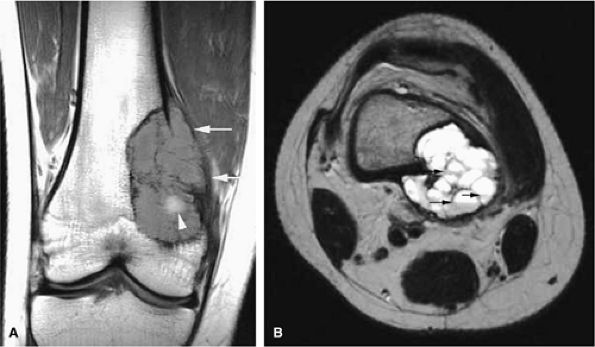

FIGURE 14-68 ● Telangiectatic osteosarcoma. (A) Coronal T1-weighted and (B) axial T2-weighted images show intraosseous and extraosseous tumor extension (white arrows) with heterogeneous cystic hemorrhagic components (white arrowhead) and fluid–fluid levels (black arrows).

Telangiectatic osteosarcomas are especially difficult to assess histologically because the viable cells and anaplastic cells are obscured by hemorrhage and necrosis or camouflaged within benign reactive cells of the walls, which simulates an aneurysmal bone cyst (Fig. 14-67).72,74 It was thought to have a worse prognosis than conventional osteosarcoma, but now the prognosis is considered similar. On radiographs, the telangiectatic variant appears lytic because of the lack of demonstrable bone production. MR images show an aggressive, destructive lesion, usually accompanied by an associated soft-tissue mass. The inhomogeneity of signal intensity, with both low- and high-signal-intensity areas on T1- and T2-weighted images and fluid–fluid levels, reflects the high degree of vascularity and the presence of large hemorrhagic cystic spaces (Fig. 14-68).